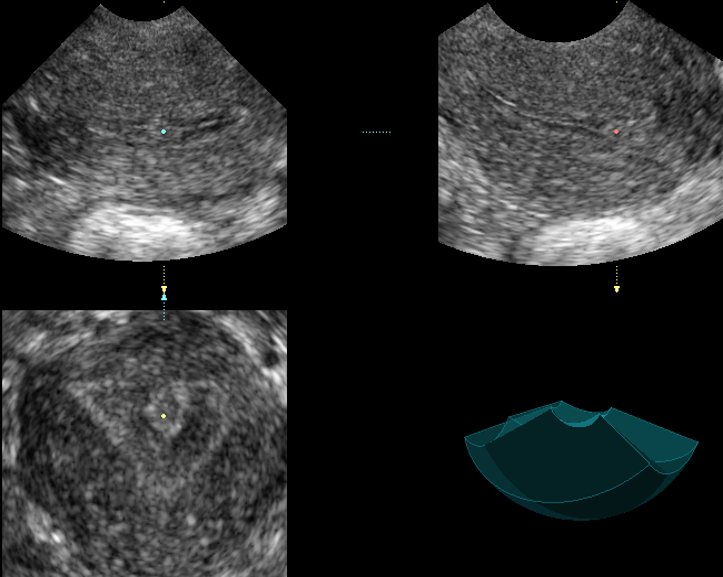

Современные экспертные УЗИ сканеры дают возможность проводить исследования всех органов в 3D. Это позволяет, используя полученный массив данных, получать диагностические сечения в любой плоскости, недоступной для обычного 2D УЗИ. Наиболее интересной является фронтальная. Например, визуализация полости матки. Диагностическая возможность выявления пороков развития превосходит все другие методы (рентгеновские и МРТ). Метод также позволяет уточнить положение ВМК (спирали) в полости матки, расположение миоматозных узлов, расположение плодного яйца на малых сроках, полипов. Сегодня современное экспертное ультразвуковое исследование невозможно без использования 3D УЗИ.